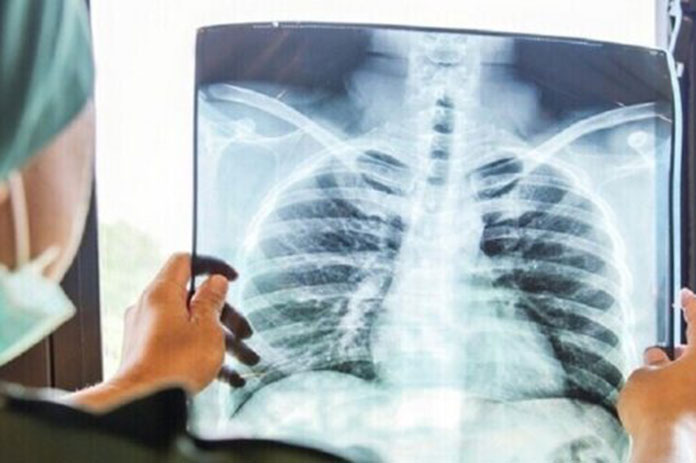

هوى الشام| من المعروف أن تدخين السجائر هو السبب الرئيسي لسرطان الرئة، ولكن، في الواقع، أقلية فقط من المدخنين يصابون بهذا المرض.

وتشير دراسة قادها علماء في كلية ألبرت أينشتاين للطب ونشرت على الإنترنت في مجلة Nature Genetics، إلى أن بعض المدخنين قد يكون لديهم آليات قوية تحميهم من سرطان الرئة عن طريق الحد من الطفرات. يمكن أن تساعد النتائج في تحديد هؤلاء المدخنين الذين يواجهون خطرا متزايدا للإصابة بالمرض، وبالتالي يستلزمون المراقبة الدقيقة بشكل خاص.

وقال الدكتور سيمون سبيفاك، المؤلف الرئيسي المشارك للدراسة، أستاذ الطب وعلم الأوبئة وصحة السكان، وعلم الوراثة في كلية ألبرت أينشتاين للطب، وأخصائي أمراض الرئة في نظام مونتيفيوري الصحي : “قد تكون هذه خطوة مهمة نحو الوقاية والكشف المبكر عن مخاطر الإصابة بسرطان الرئة وبعيدا عن الجهود الهائلة الحالية اللازمة لمكافحة المرض في المرحلة المتأخرة”.

لطالما كان يُفترض أن التدخين يؤدي إلى سرطان الرئة عن طريق تحفيز طفرات الحمض النووي في خلايا الرئة الطبيعية.

وقال الدكتور سبيفاك: “تعيش خلايا الرئة هذه لسنوات، أو حتى عقود، وبالتالي يمكن أن تتراكم الطفرات مع تقدم العمر والتدخين. ومن بين جميع أنواع خلايا الرئة، هذه هي أكثر أنواع الخلايا عرضة للإصابة بالسرطان”.

وأوضح الدكتور سبيفاك: “هذا يؤكد تجريبيا أن التدخين يزيد من خطر الإصابة بسرطان الرئة عن طريق زيادة تواتر الطفرات، كما افترض سابقا. وهذا على الأرجح أحد أسباب إصابة عدد قليل من غير المدخنين بسرطان الرئة، بينما يصاب 10% إلى 20% من المدخنين مدى الحياة”.